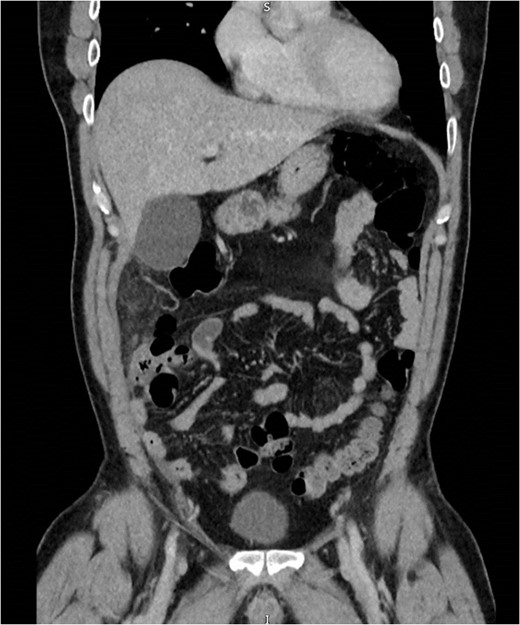

An initial differential diagnosis was made as cholecystitis. Appropriate intravenous antibiotics were commenced. An abdominal ultrasound demonstrated a thin-walled gallbladder without gallstones and a normal common bile duct caliber. There was however a trace of free fluid in the right iliac fossa. The sonographer was unable to identify a normal appendix. The following afternoon a CT scan of his abdomen and pelvis demonstrated fluid in the right iliac fossa as well as his rectovesicular pouch. The appendix was normal, but there was tissue stranding adjacent to the caecum and ascending colon to the tip of the liver (Figs 1 and 2).

Abdominal CT demonstrating soft tissue stranding and odema inferior to a normal gallbladder, extending to the caecum.